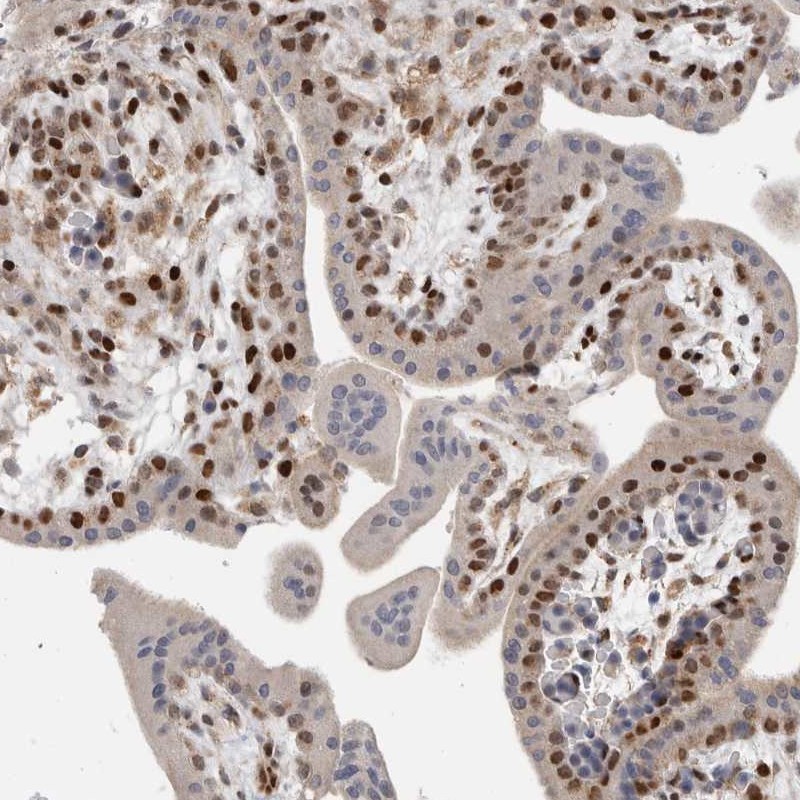

Immunohistochemical staining of human placenta shows strong nuclear positivity in trophoblastic cells.